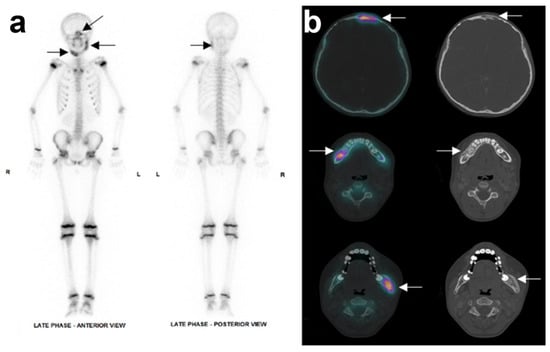

A new CT scan showed that both sides of the mandible were affected, including the right corpus and left ascending ramus, leading to an expansive deformity of the bone. No sequestration was found. Another affected area was detected in the right frontal bone (Figure 2). A bone SPECT (single photon emission computed tomography) registered with this CT scan confirmed the location and areas of metabolic activity corresponding to areas of mandibular and frontal osteosclerosis and osteolysis. No other bone lesions were identified (Figure 3).

Figure 3. Nuclear X-ray of the patient’s initial state: (a) Whole-body bone scintigraphy showed three areas of increased uptake (hot spot) in the facial skeleton: in the body of the right mandible, in the angle and ascending ramus of the left mandible, and in right frontal sinus. (b) SPECT registered with CT scan displaying, from top to bottom line, the increased uptake in frontal sinus, right and left mandible, respectively. SPECT: single photon emission computed tomography.